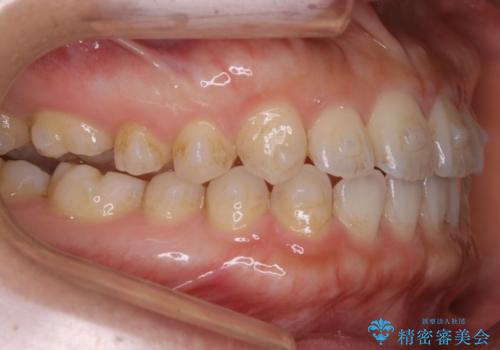

- 矯正治療を主訴にご来院されました。

すきっ歯と噛み合わせの治療をしたいとのことで、インビザラインを用いて矯正治療を行うこととなりました。

すきっ歯の場合、ガタつきを治したりするのに必要なスペースが最初から空いているため、そのスペースを利用して比較的短期間で効率よく治療を進めることが可能となります。

初診時の写真では一見噛み合わせには問題がないように見えても、実際に精密な検査を行うと改善すべき点が見つかる場合も多くあります。